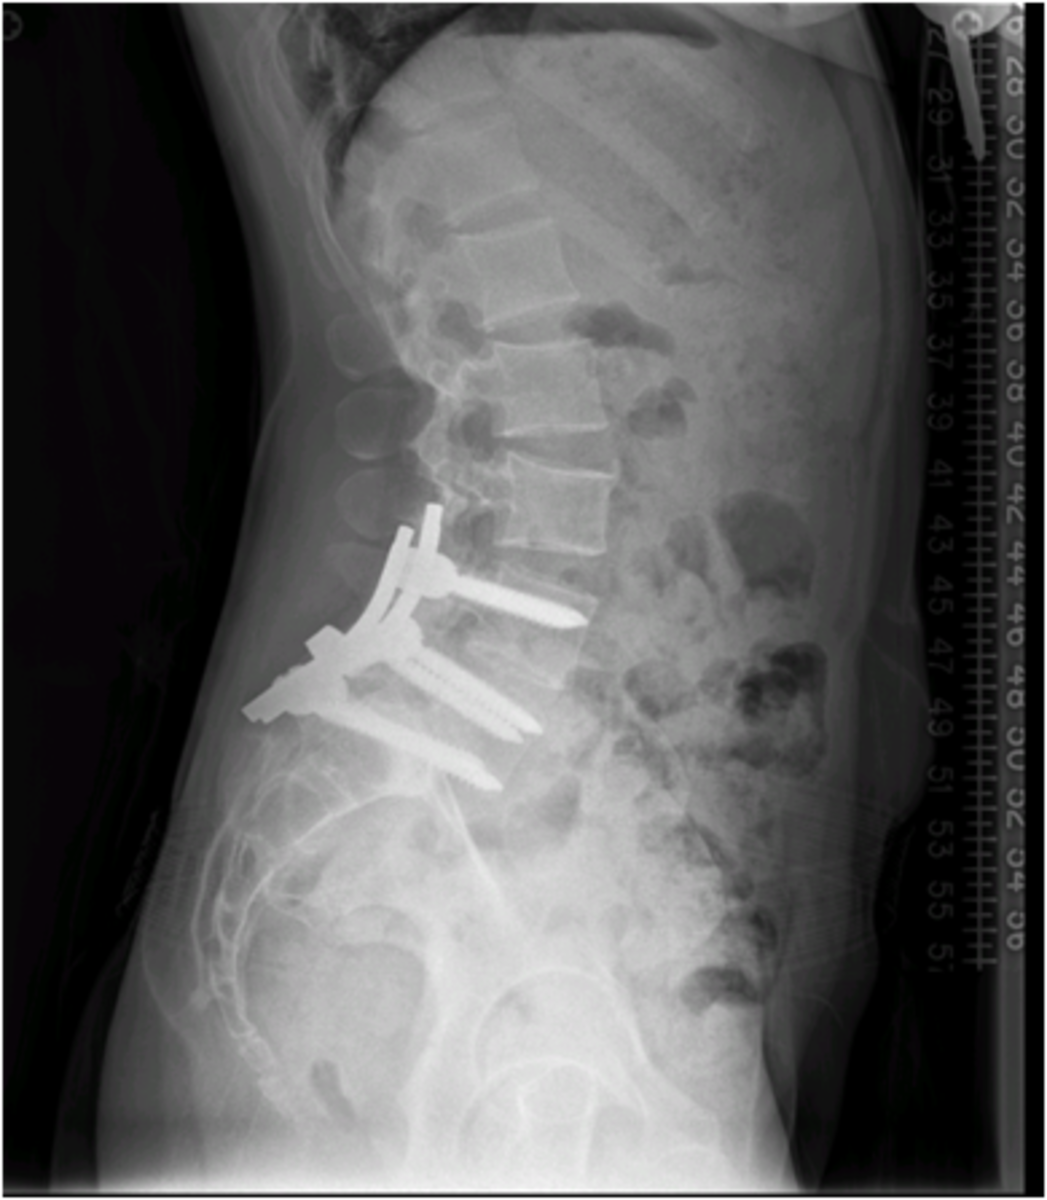

Ultimately, the surgery was successful at correcting Bloomberg’s spine by fusion with metal plates and screws. As a dedicated athlete, her typical reaction to previous injuries had been to push through and get back in the tack as soon as she could, no matter the odds or the doctor’s orders. This time was different. She spent her first few months in bed with an outlook on recovery that she had never allowed herself to recognize.